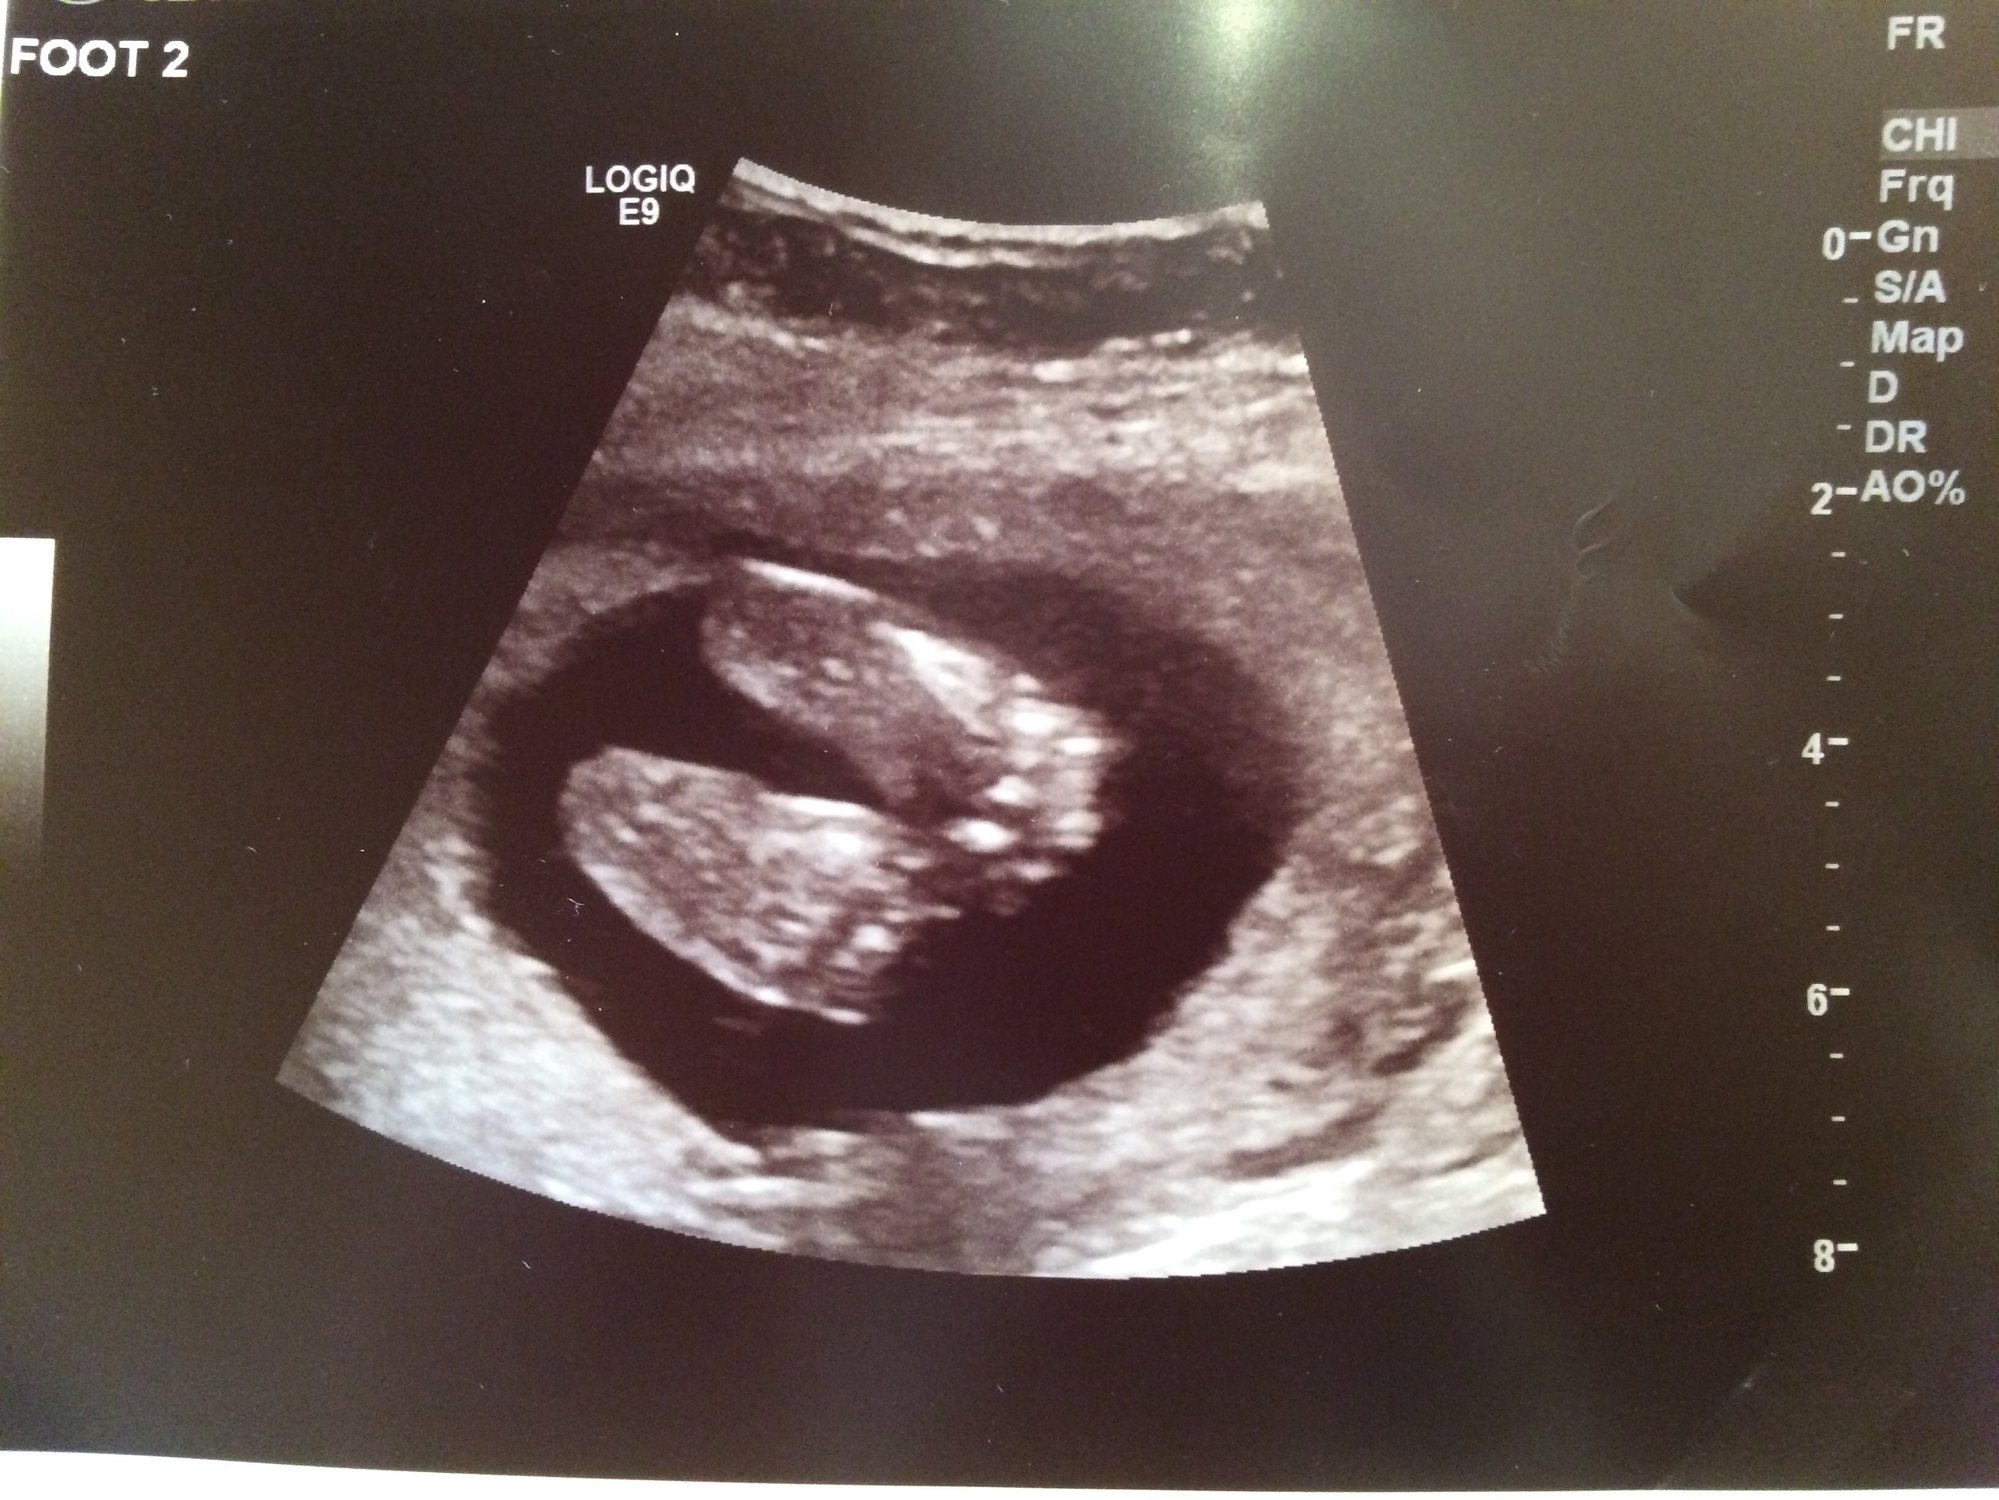

Hoping this works-ive never uploaded on here from a phone. This is sweet baby at 17+5 for our anatomy scan. We aren't finding out sex, so still using interchangeable pronouns and avoiding calling the baby "it". Babies nickname has been Batman since the beginning (cause....why not). Since we didn't get a great face shot to do measurements, I get to go back in 8 weeks for another. Which I am secretly thrilled about. This picture is SUCH a change from babies first photo shoot at 5+6!